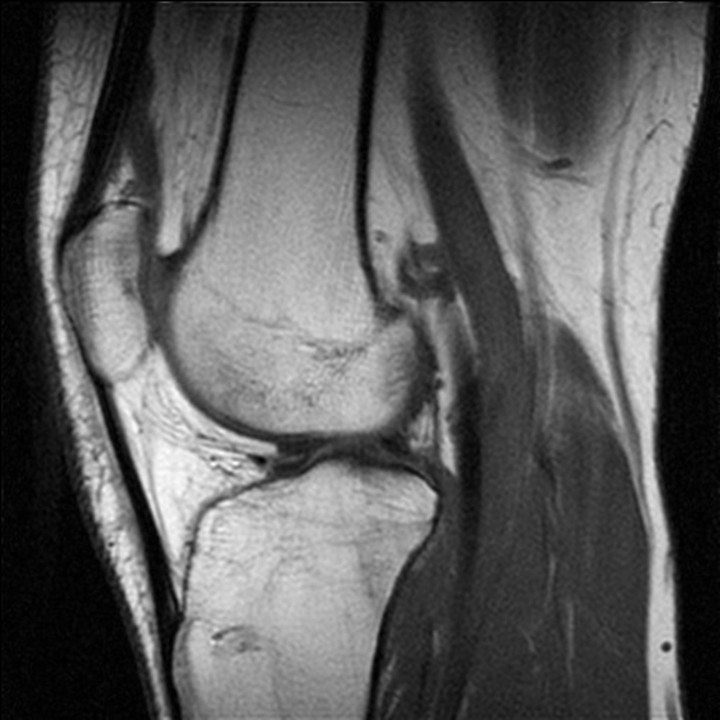

Запитання 49

СУГЛОБ СКЛАДНИЙ. СУГЛОБОВА КАПСУЛА ТОНКА, УТВОРЮЄ БАГАТО СУМОК, ЯКІ СПОЛУЧАЮТЬСЯ ІЗ СУГЛОБОВОЮ ПОРОЖНИНОЮ. ЦЕ СПРИЯЄ ПЕРЕХОДУ ЗАПАЛЬНИХ ПРОЦЕСІВ (Є ДІАГНОЗ: БУРСИТ). ДЕ ВИ БАЧИТЕ ЦЕЙ СУГЛОБ.

варіанти відповідей

Запитання 51

РОЗПІЗНАЙТЕ СУГЛОБ, ЯКИЙ ЗАБЕЗПЕЧУЄ РУХИ ГОМІЛКИ.

РОЗПІЗНАЙТЕ СКЛАДНИЙ СУГЛОБ, ЯКИЙ СКЛАДАЄТЬСЯ З ТРЬОХ КІСТОК, ОДНА З ЯКИХ РОЗТАШОВАНА В СУХОЖИЛКУ ЧОТИРИГОЛОВОГО М'ЯЗА СТЕГНА.